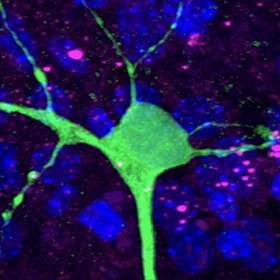

In a 3D model of a brain circuit, the sick protein (pink) responsible for Huntington’s disease spreads from mouse cells to a healthy human neuron.

Pecho-Vrieseling and co-first author Claus Rieker (a postdoc who recently moved to the Nestlé Institute of Health Sciences) inserted healthy human neurons—derived from embryonic and induced pluripotent stem cells—into the dish, waited for the newcomers to integrate into the neural circuit and monitored the result. Initially, the sick protein, which they had labeled pink, was confined to the mouse neurons. After a few weeks, however, it began to show up as pink specks in the healthy human neurons, which proceeded to change shape and look stressed.